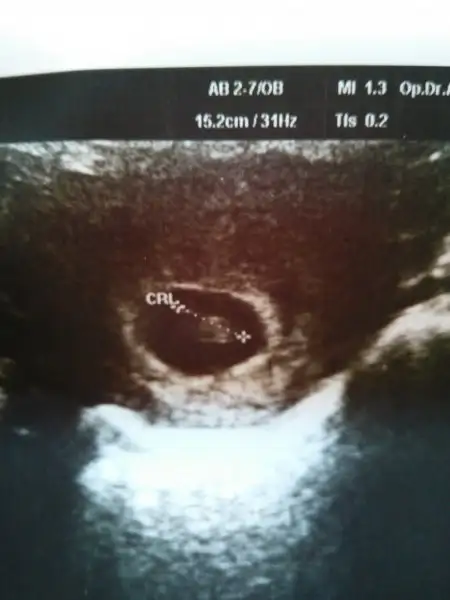

Evet ilk evladımız kız. Gönül ister bir kızımız var birde oğlumuz olsun. Ama rabbim ne verirse sağlıklı versin tabi kiGerçekten ilk hamileliğinde bebek ile plasenta uzak. Plasenta sağda. İlk bebeğin kız diye hatırlıyorum. Bu hamileliğinde plasenta solda. Teoriye göre erkekk. Hadi hayırlısı :)

Öğrendin mi cinsiyetiniRamzi teorisine göre ( bilimsel bir araştırma sonucuymuş ve %85 doğruluğu varmış). İlk 6-8 haftalık ultrason görüntüsüne göre bebeğin kesenin içersinde soldan ya da sağdan girişine göre cinsiyet tahmini yapılıyor. Bilimsel olunca tecrübeli annelerimiz yada anne adaylarımızdan yardım istiyoruz. Doğruluğu var mı öğrenmek adına :) Bizleri aydınlatırsanız çok seviniriz. bu teorieye göre;

Vajinal muayeneyle bakıldıysa eğer;

Sağdan girmiş gözüküyosa aslında solmuş ve ERKEK,

Soldan girmiş gözüküyosa aslında sağmış ve KIZ ,

Karından bakıldıysa eğer,

Soldan girmiş gözüküyosa gerçektede solmuş ve ERKEK,

Sağdan girmiş gözüküyosa gerçekte de sağmış ve KIZ,